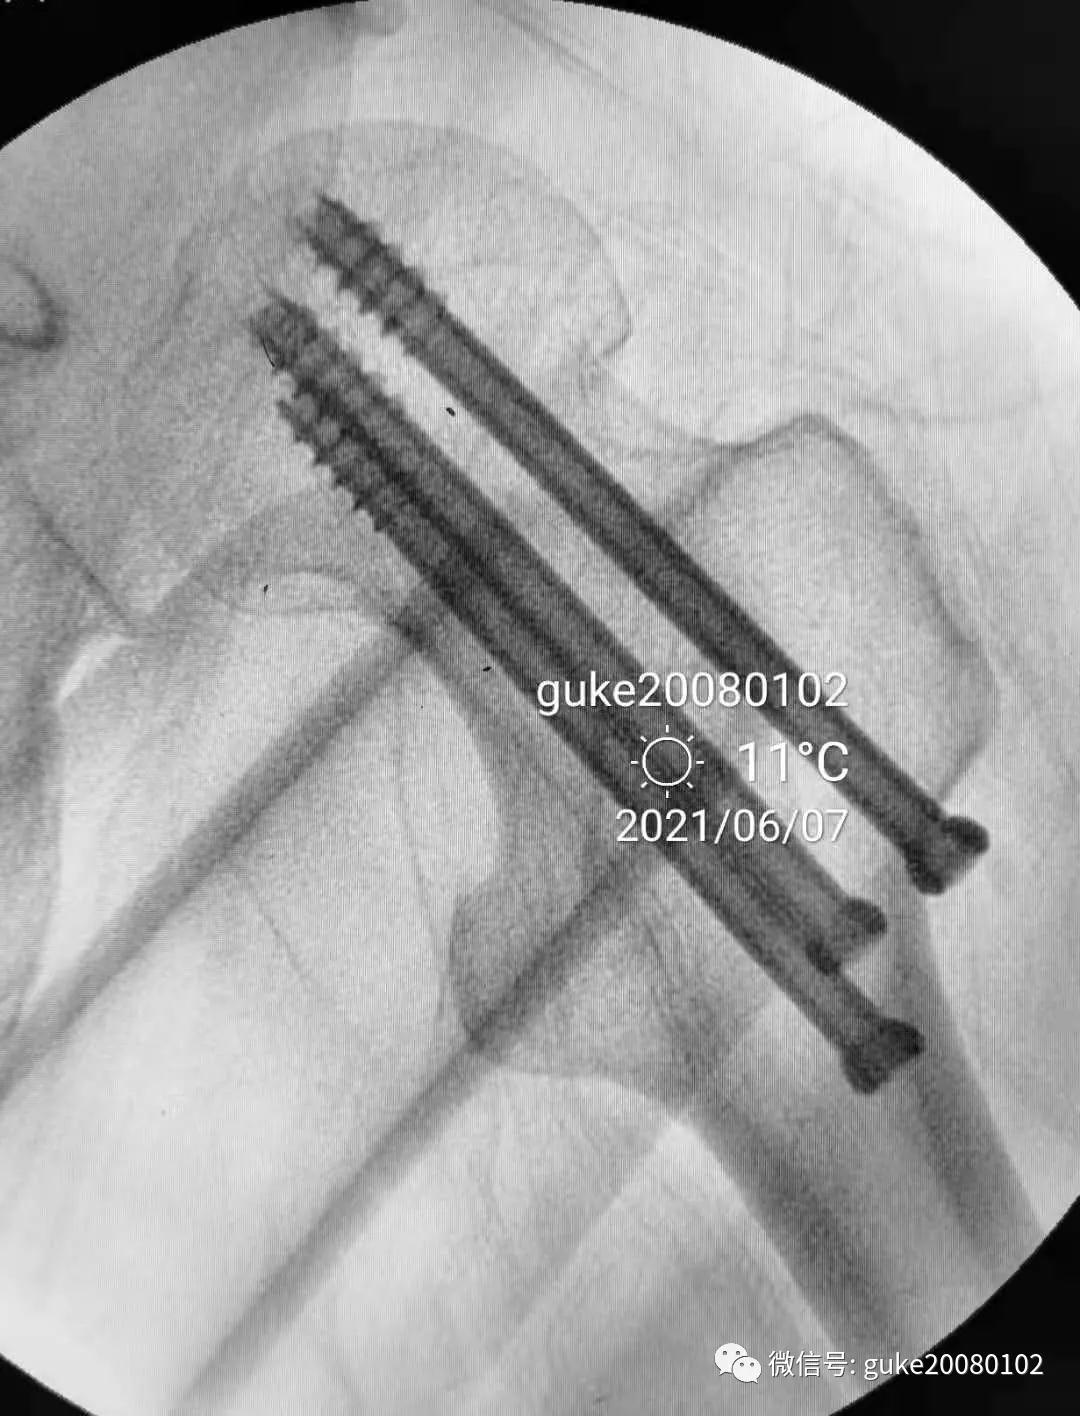

1.顺导针切开皮肤后,空心钻大转子外侧壁开口。

2.拧入三枚直径7.3mm空心钉,并逐步加压,稳定骨折断端。

最后透视: